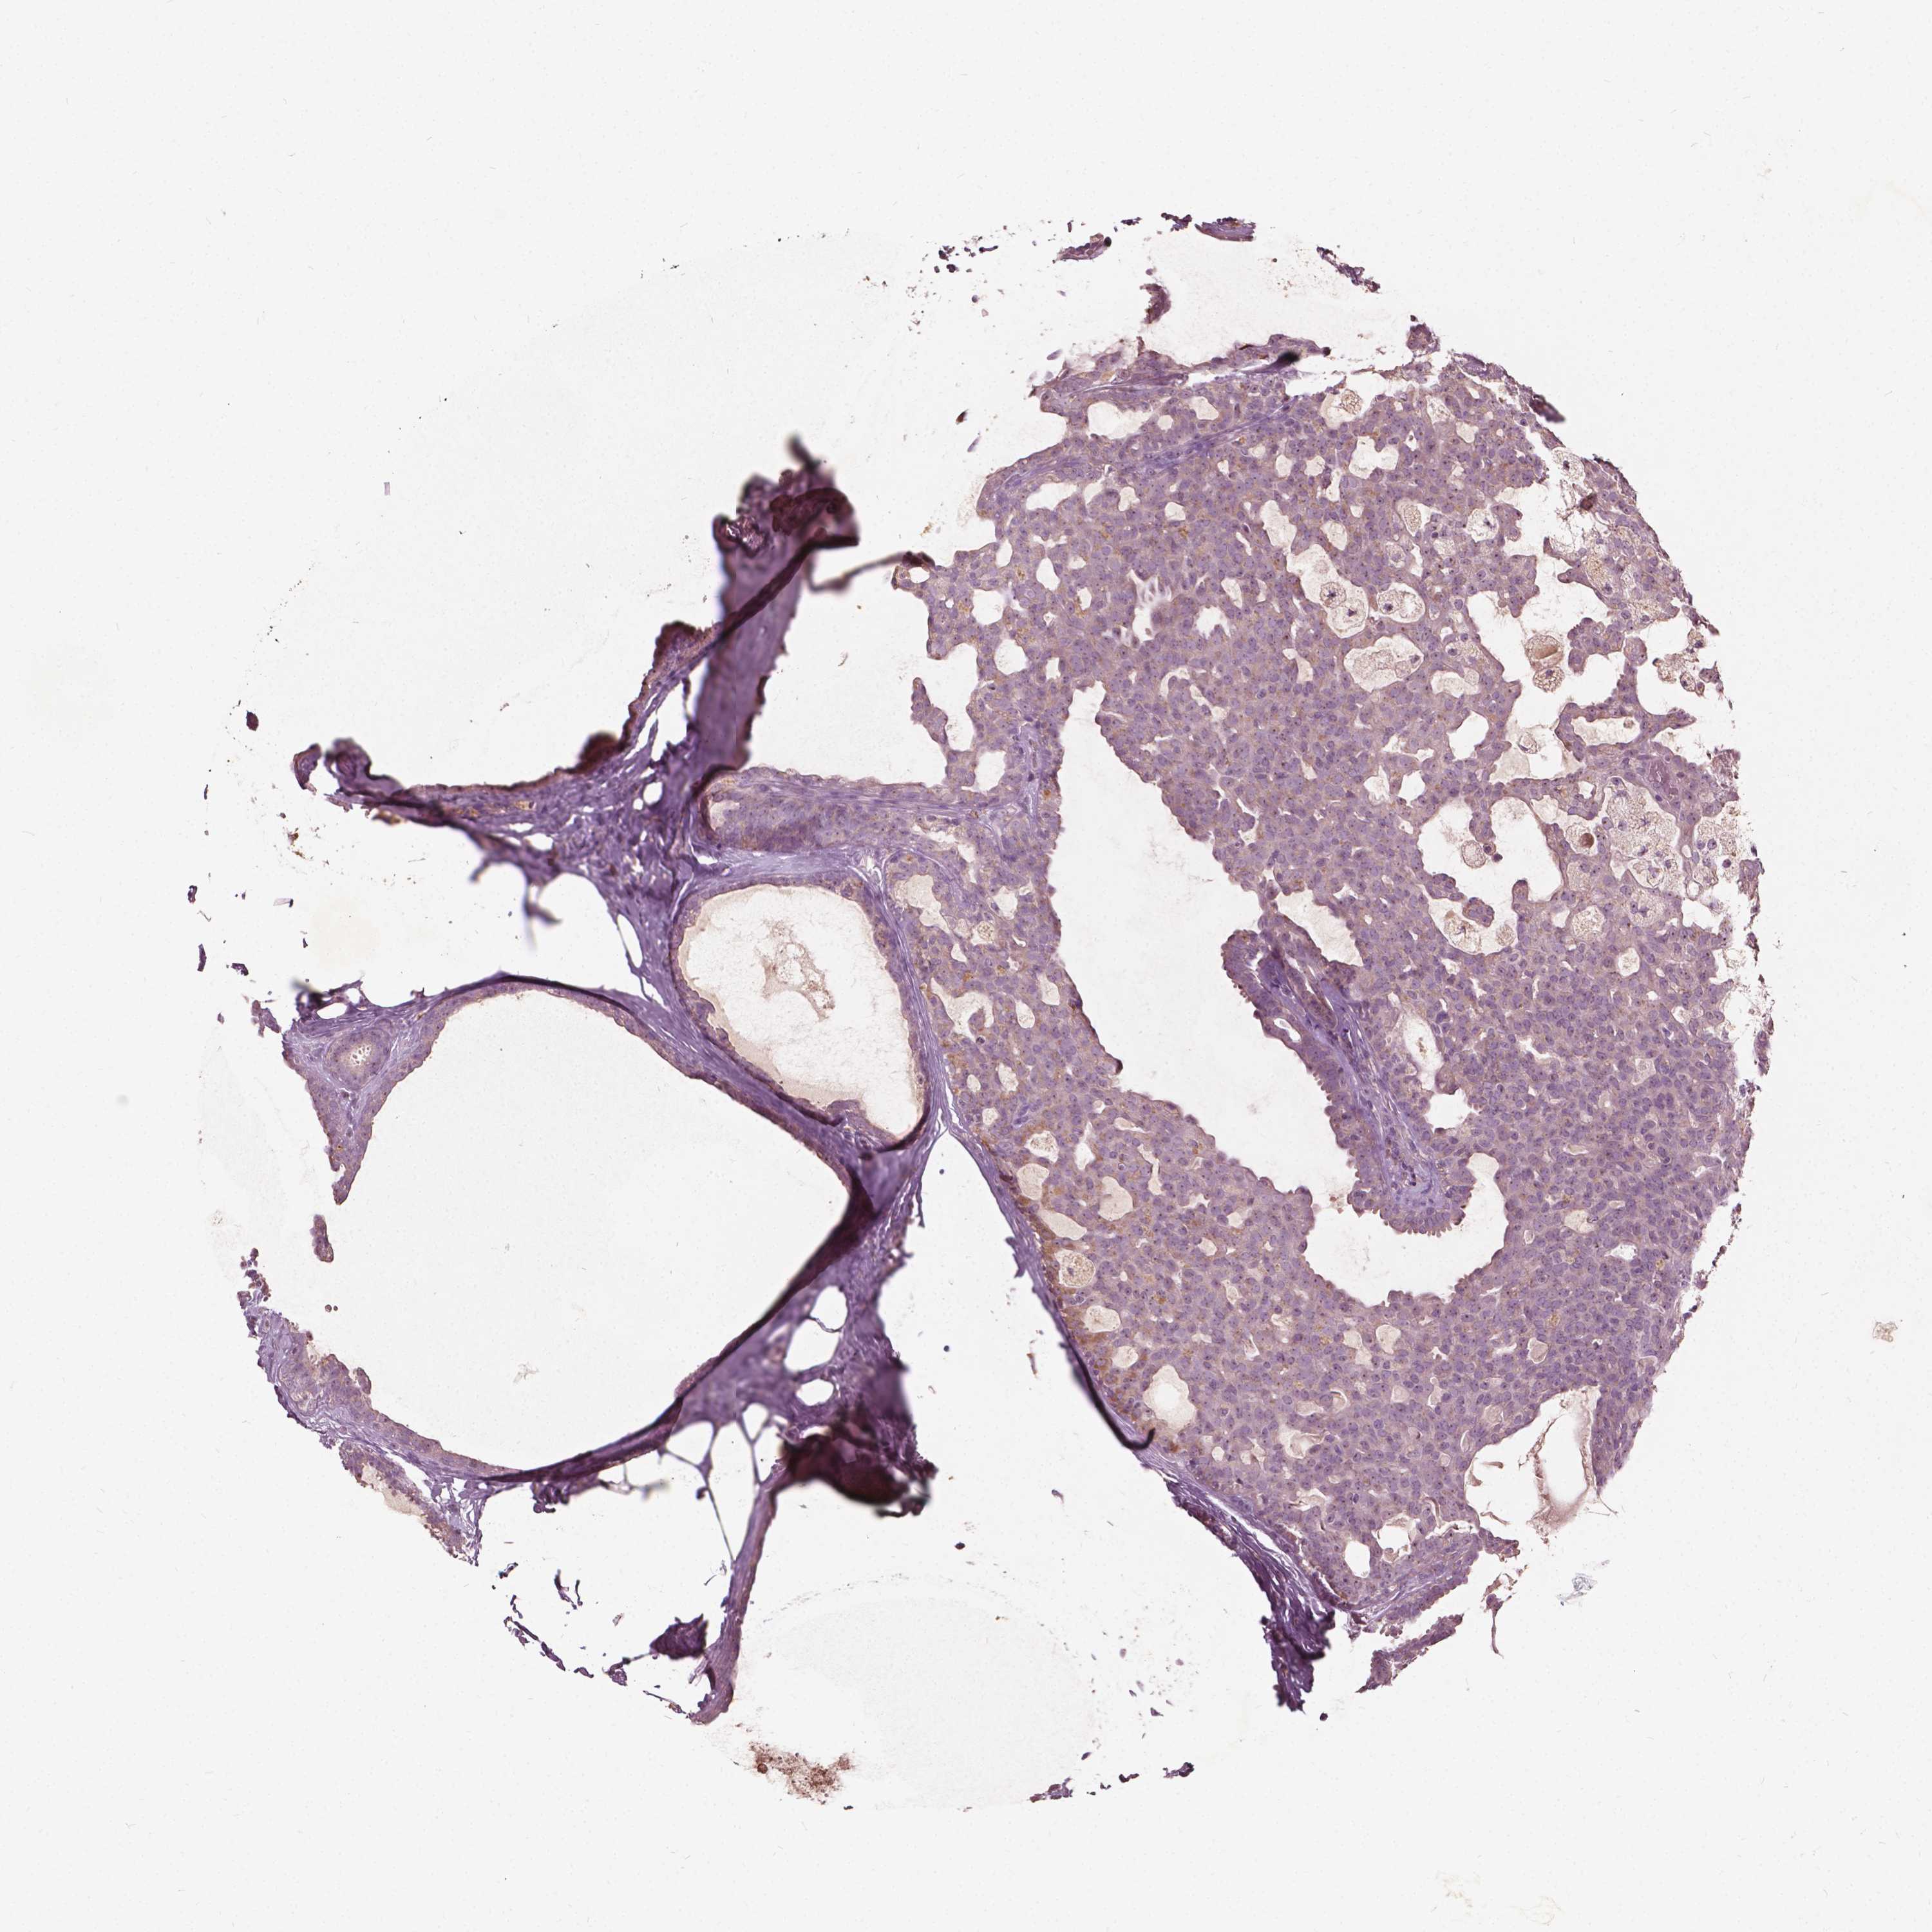

CANCER BREAST CANCER Show tissue menu

BRCA TCGA BRCA VALIDATION PROTEIN EXPRESSION

Breast cancer

Human cancer